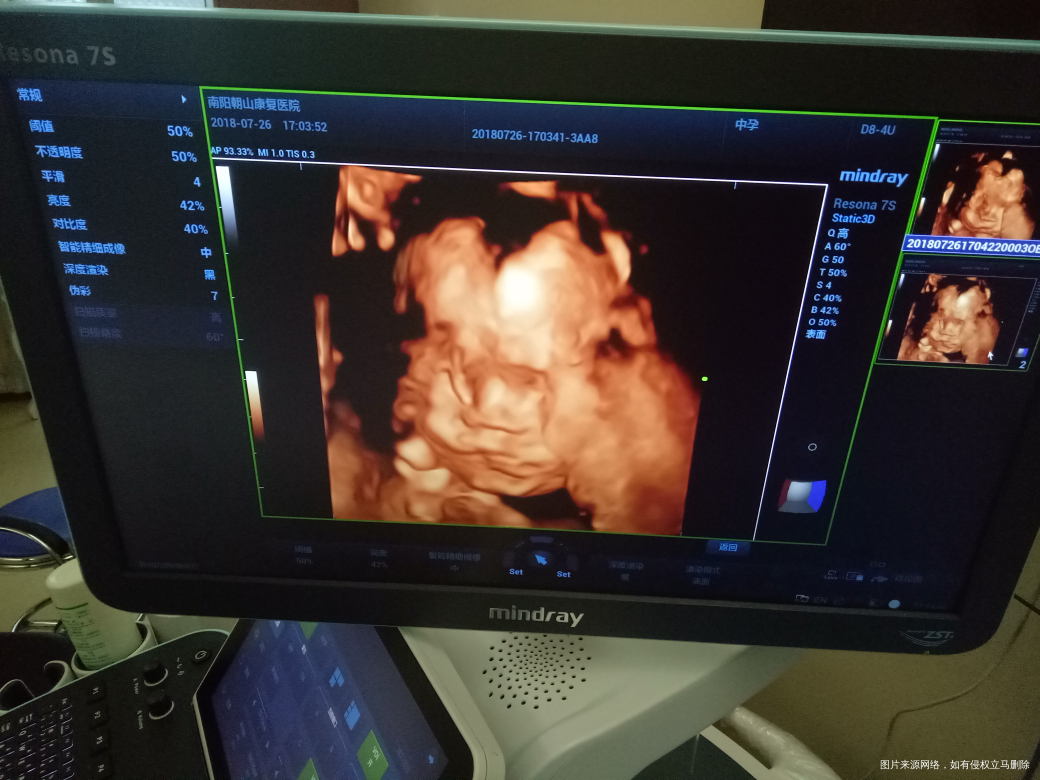

二胎四维图,大脸盘,大家猜猜是男是女,自己已知[开心]

脐带挡到脸了